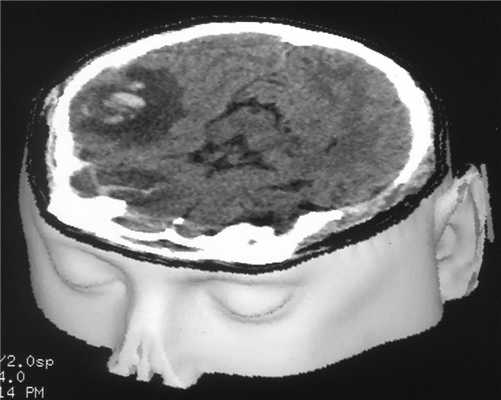

КТ головного мозга. Ушиб головного мозга тяжелой степени, внутримозговые гематомы обеих лобных долей.

КТ головного мозга. Острая эпидуральная гематома в левой затылочной области с дислокацией головного мозга и его сдавлением.

КТ головного мозга. Острая субдуральная гематома в правой лобно-теменно-височной области с дислокацией головного мозга и его сдавлением.